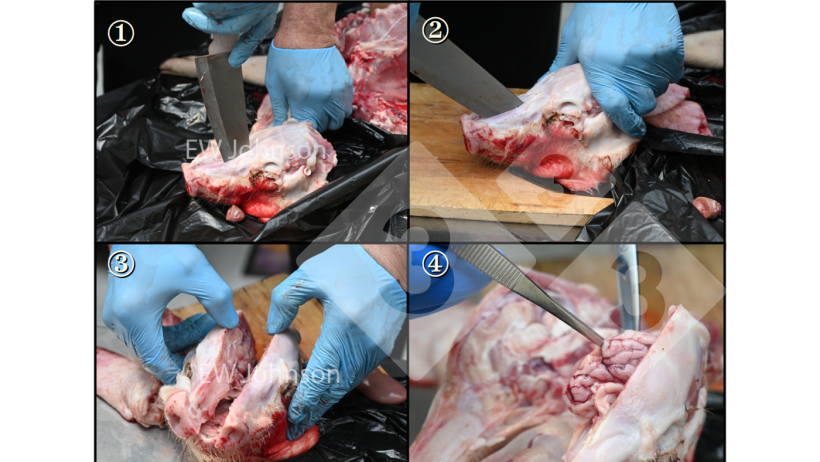

L'histopathologie grossit ce qui peut être vu à l'œil nu. Elle aide à interpréter les résultats d'autres tests et peut souvent fournir un diagnostic.

Le processus de préparation des échantillons pour l'histopathologie prenait auparavant plusieurs jours, mais peut désormais être réalisé en 4 heures si nécessaire.

Parfois, nous pouvons trouver des choses que nous ne nous attendions pas à voir (figure 3).

Figure 3. Muscle cardiaque avec hémorragie, nécrose hyaline et alignement des noyaux montrant une carence en vitamine E et en sélénium. Ces porcs n'auraient pas un système immunitaire fonctionnant normalement.